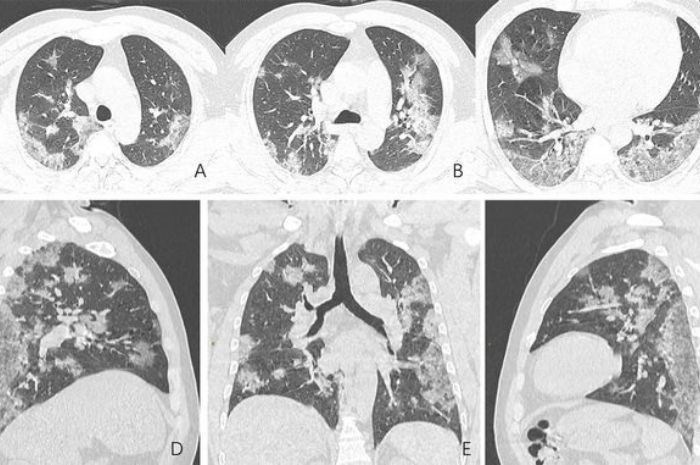

Akciğerlerde kontrol dışına çıkmış olan enflamasyon akut yaygın alveol hasarına yol açar ki bu durum akciğer röntgeninde buzlu cam ve yoğunluklar şeklinde görülür.

ARDS akut faza ilerlediğinde alveoller ödem sıvısı ile dolar, hücreler arası kısım olan interstisyumda enflamasyon ve kompresyon atelektazileri gelişir.

EK 2 (20.4.2022): Progression to ARDS in COVID-19: Here’s What It Looks Like Diffuse alveolar damage in acute respiratory distress syndrome.

Kaynak: https://consultqd.clevelandclinic.org/progression-to-ards-in-covid-19-heres-what-it-looks-like/